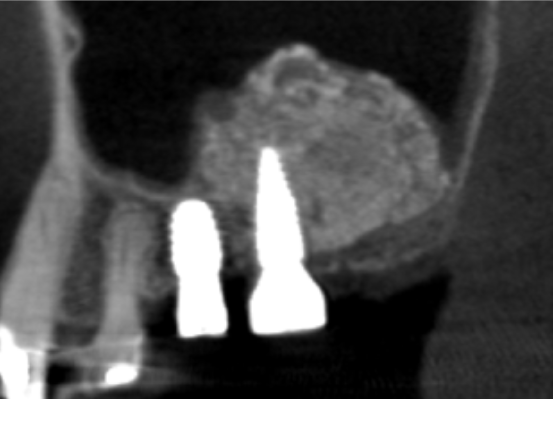

症例3

| 項目 | 詳細 |

|---|---|

| 患者様データ | 68歳 女性 |

| 来院時の主訴 | 「普通に食事がしたい。」 |

| 医院の診断 | 歯牙欠損、重度の顎堤欠損、角化歯肉不足 |

| 通院期間 | 10か月 |

| 来院回数 | 15回 |

| 治療費 | 総額:1,005,000円(税抜) 【内訳】 GBR(骨再生手術)250,000円、インプラント埋入手術250,000円、2次手術+FGG(遊離歯肉移植術)55,000+60,000円、仮歯30,000円、インプラント上部構造(セラミッククラウン)170,000円、歯冠長延長術70,000円、セラミッククラウン120,000円 |

| リスクと副作用 | 定期的なメンテナンスが必要、術後若干の腫れと痛み |

| ここがこだわりのポイント!☝ | 骨量不足により他院にてインプラントを断られた患者様です。大規模な骨造成を行うことでインプラント治療が可能になりました。 |